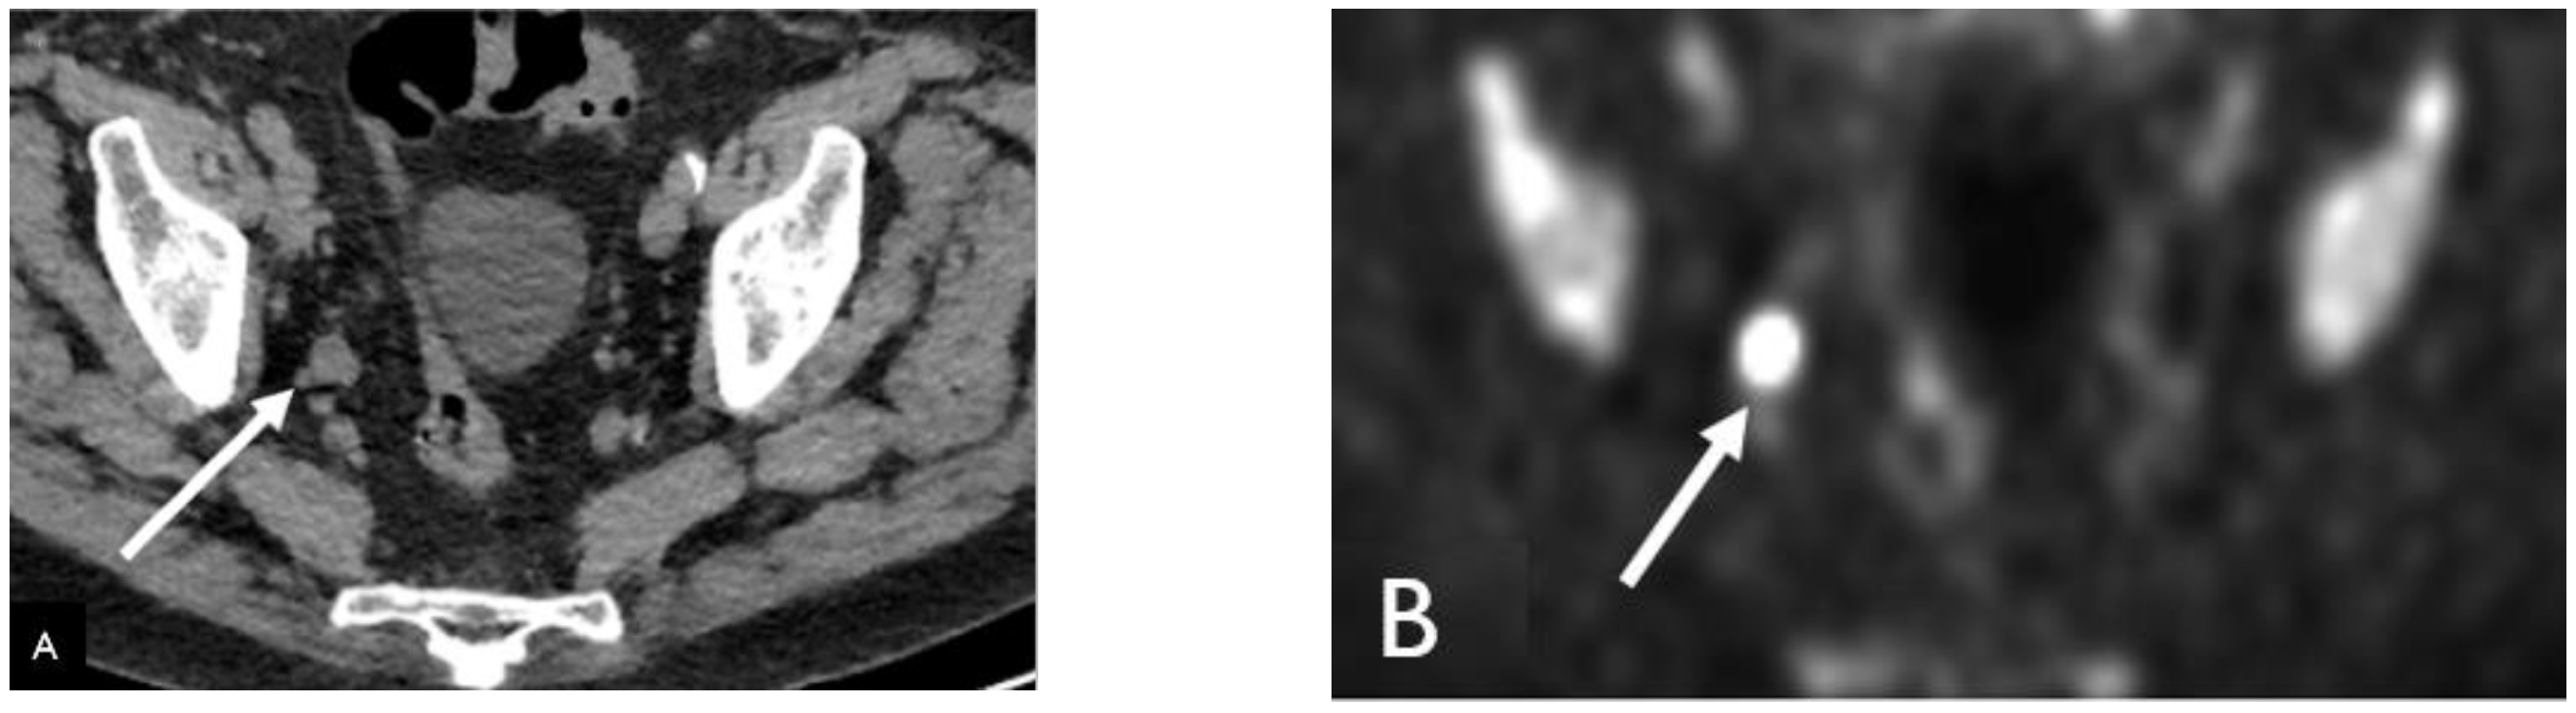

Detection of Loco-Regional Disease and Distant Metastases

- Songmen, S.; Nepal, P.; Olsavsky, T.; Sapire, J. Axumin Positron Emission Tomography: Novel Agent for Prostate Cancer Biochemical Recurrence. J. Clin. Imaging Sci. 2019, 9, 49. [Google Scholar] [CrossRef] [PubMed]